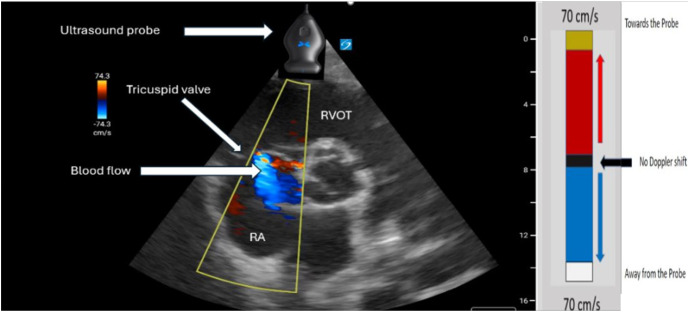

Point-of-care ultrasound (POCUS) is a powerful diagnostic tool that combines image acquisition with bedside interpretation, enabling physicians to make rapid diagnoses at the bedside (1). Over the last decade, the popularity of POCUS has surged because of its versatility and the immediate insights it provides in clinical decision making (1). However, basic POCUS does not provide important hemodynamic information, such as intracardiac pressures, stroke volume, or valvular regurgitation assessment. Critical care echocardiography (CCE) becomes indispensable as a specialized application of POCUS focused on using Doppler techniques to provide detailed hemodynamic assessments in critically ill patients (2). Teaching hemodynamic evaluation in CCE, such as estimating right ventricular systolic pressure (RVSP), is a challenging yet essential aspect of modern critical care education. RVSP is used to assess the presence of pathologic elevation in right ventricular afterload, which has significant clinical implications for critically ill patients. Deriving RVSP requires understanding ultrasound physics, fluid mechanics, and Doppler techniques and mastery of cardiac image acquisition (3-4). These complex skills are not just important but crucial for effectively managing critically ill patients in the intensive care unit (ICU). In this edition of "How I Teach," we introduce our methodology for instructing learners in our ICU on RVSP estimation using CCE. We use hands-on ultrasound training and e-learning strategies to optimize knowledge retention, ensure accurate interpretation, and promote practical application.